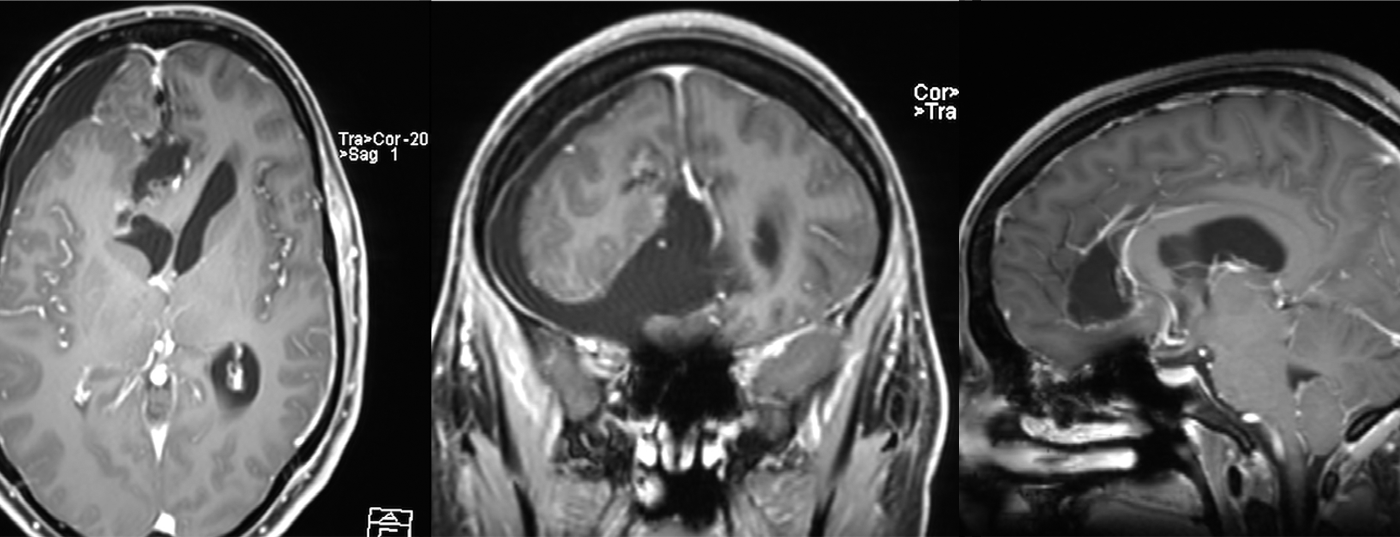

Fallbericht: Eine 31-jährige, bis anhin internistisch gesunde Frau wurde aufgrund einer zunehmenden Orientierungslosigkeit und Verwahrlosung zur psychiatrischen Behandlung stationär eingewiesen. Sie beschrieb eine sich seit zwei Monaten akzentuierende Antriebsarmut und Einschränkung der Erinnerungsfähigkeit.